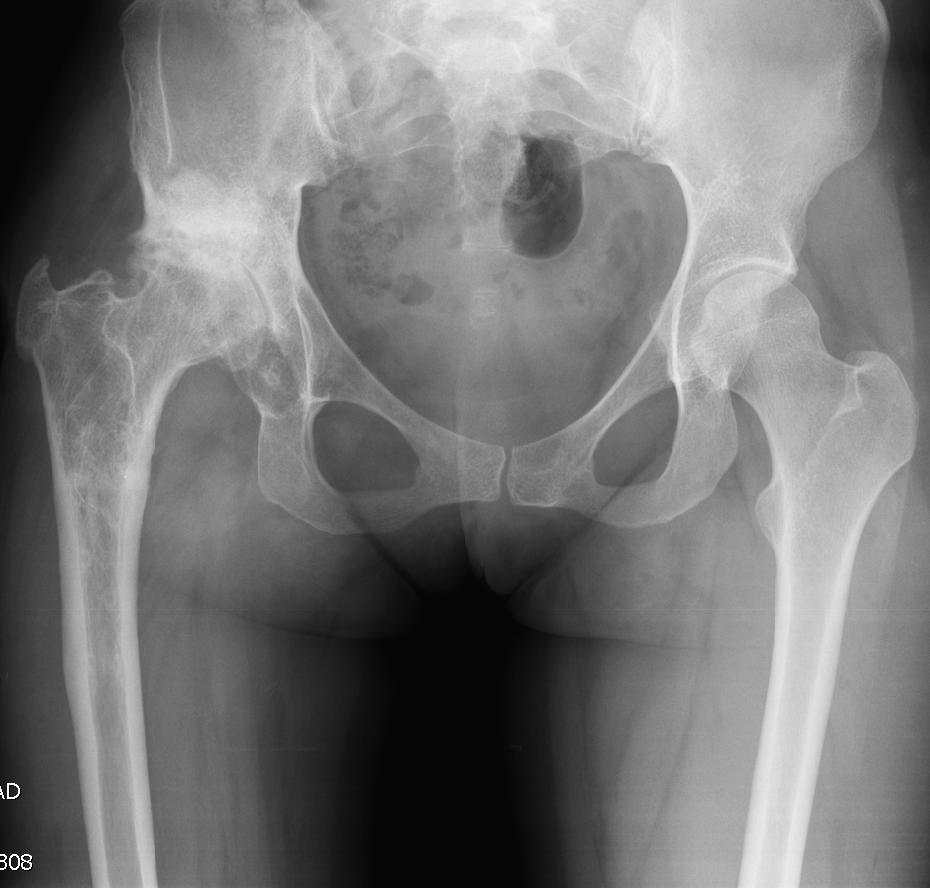

- Ендопротезиране на колянна и тазобедрена става

Основно лекувам заболявания на тазобедрена и колянна става чрез минимално инвазивно ендопротезиране, следтравматични и дегенеративни нарушения на ръката и китката и халукс валгус (популярен като „кокалчета на краката”).